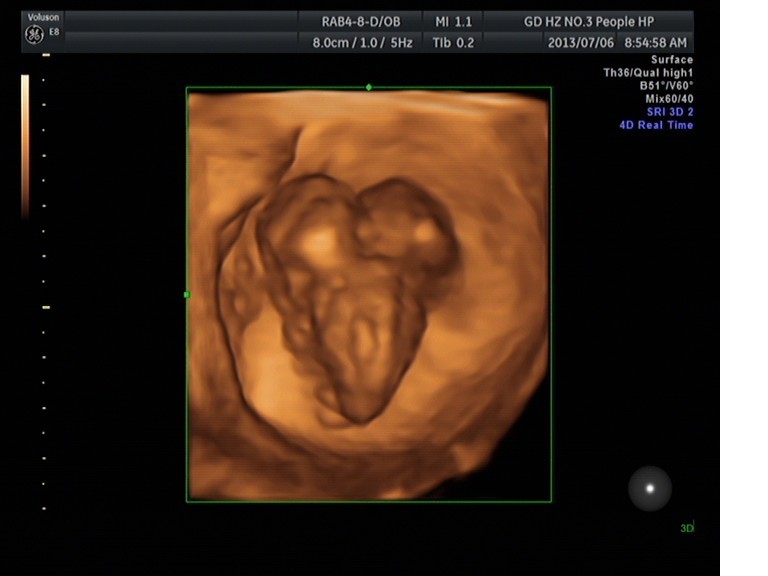

隨著環(huán)境污染日益嚴(yán)重,隨著各種地溝油的誕生,隨著各樣鎘大米的泛濫……我們的健康越來(lái)越受到威脅,很多疾病也隨之接踵而至,胎兒先天性疾病也越來(lái)越多見(jiàn)。7月6日,我院超聲科王瑤醫(yī)生在做胎兒產(chǎn)前NT篩查中發(fā)現(xiàn)一例孕約11周+的聯(lián)體雙胎。超聲所見(jiàn):增大的子宮內(nèi)可見(jiàn)聯(lián)體雙胎兒回聲,可見(jiàn)兩個(gè)胎頭不能分離,胸部及腹部融合,可見(jiàn)一個(gè)增大的心臟。

聯(lián)體嬰兒B超圖像